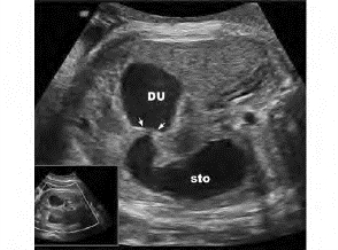

1.38.12十二、胎儿畸形